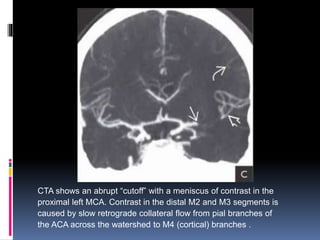

CTA shows an abrupt “cutoff” with a meniscus of contrast in the

proximal left MCA. Contrast in the distal M2 and M3 segments is

caused by slow retrograde collateral flow from pial branches of

the ACA across the watershed to M4 (cortical) branches .